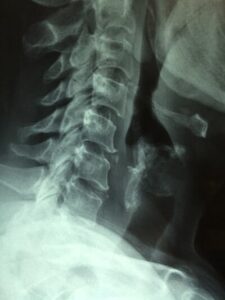

5 Common Causes Of Neck Pain

Neck Pain Causes And Treatments Dr French In Norwalk Ct